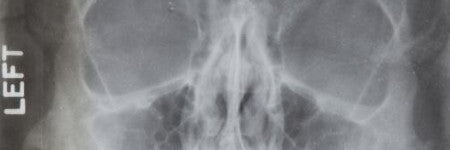

There’s also an x-ray of her nose taken on June 7, 1962, following a fall at her home. This was just two months before she died.

Dr M Gurdin referred Marilyn to the radiologist in 1962